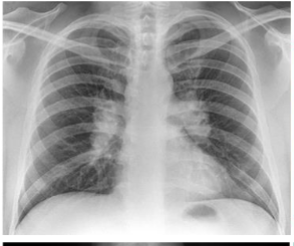

what is this?

lobar pna

multifactorial pna